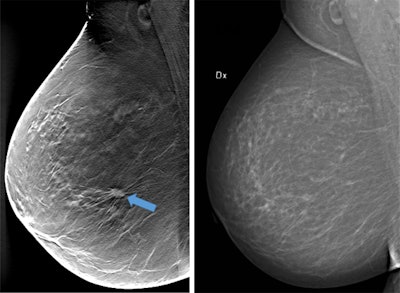

One of the hottest new technologies in breast imaging is DBT. Evidence continues to mount for the utility of DBT in breast cancer patients. While many argue DBT is ready for "prime time," in other words, breast cancer screening, others are more cautious.

DBT is a popular screening tool, and today she plans to explain how it can be implemented in the near future. She will also touch on artificial intelligence (AI) and deep-learning-based systems, including how they aid in detection and decision-making.

"Computer-aided detection (CAD) for DBT is a necessity, I would say, so I anticipate further studies including CAD," she noted. "Other software tools to aid in the reading of DBT are also of importance."